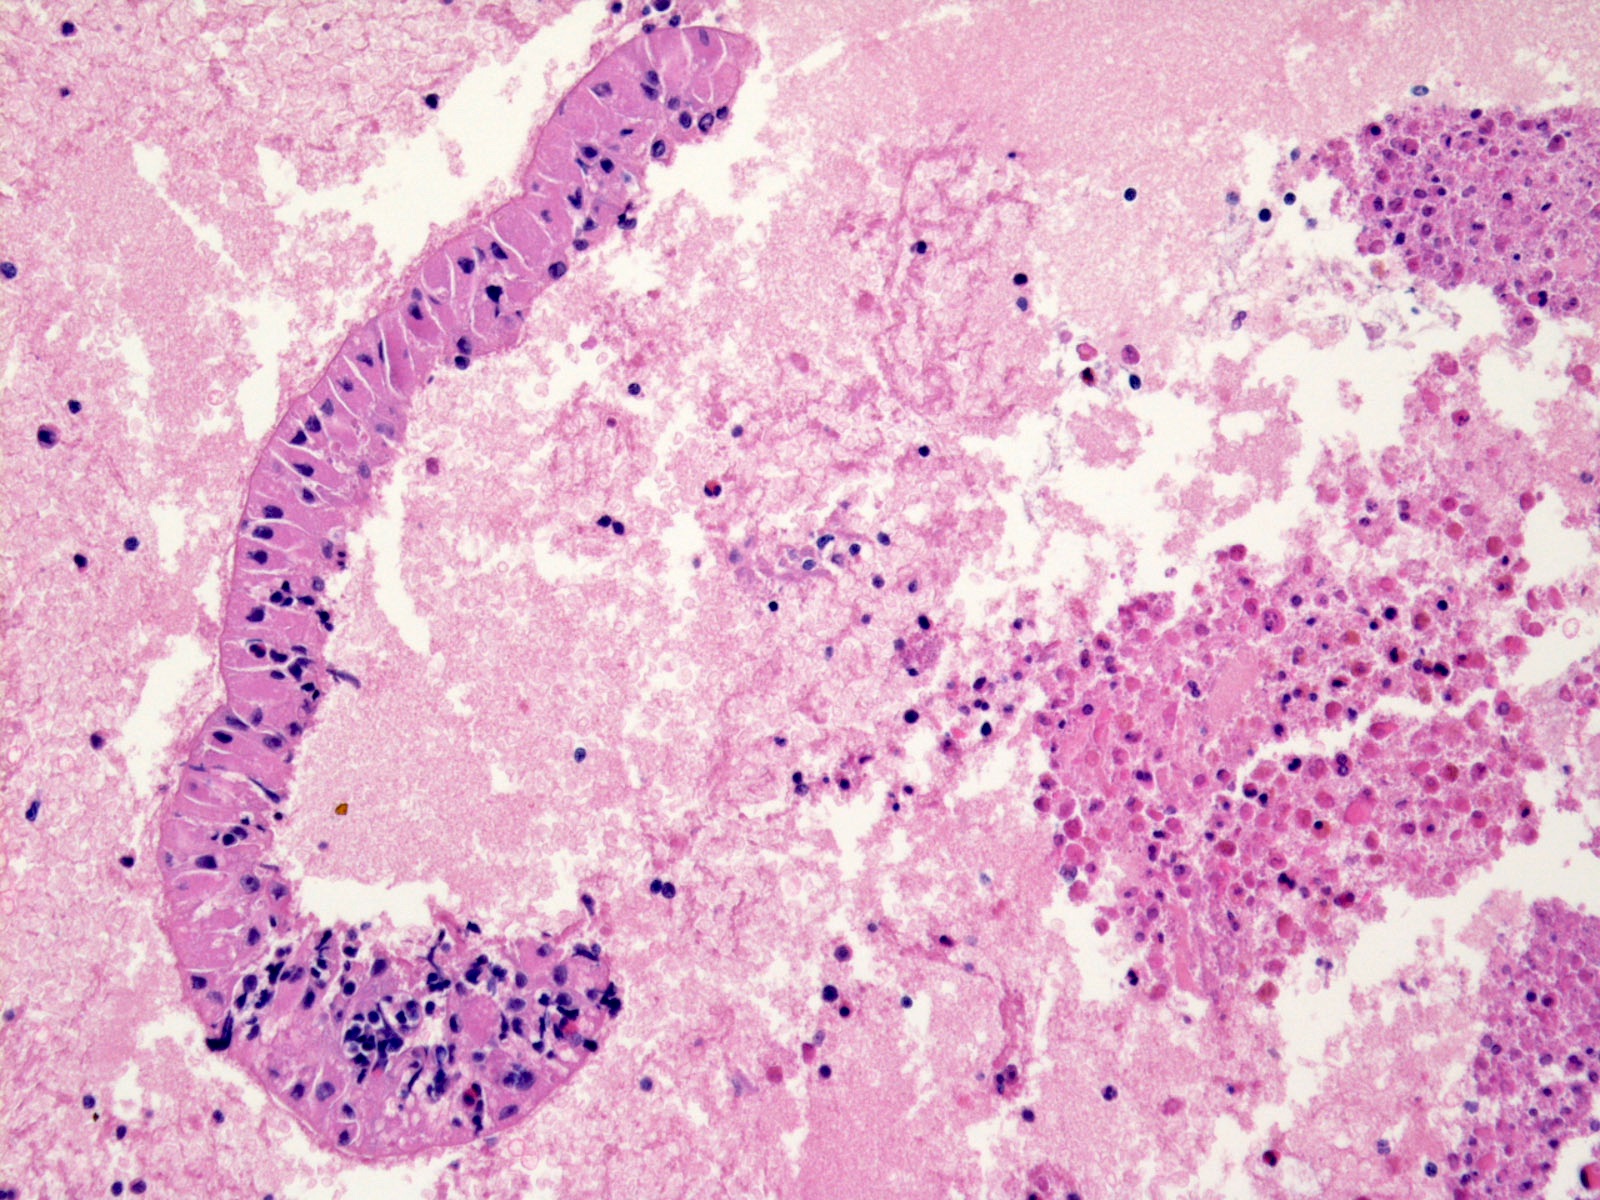

Фотографии медицинских исследований инсулиномы и синдрома Триады Уиппла